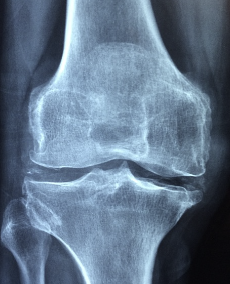

콘드로이친은 연골 생성에 중요한 성분인 글루코사민과 콘드로이틴의 합성을 돕는 물질입니다. 관절염 등의 연골 장애를 개선하고 관절 통증을 완화시키는 효과가 있으며, 스포츠 손상으로 인한 연골 손상 치료에도 사용됩니다. 주로 식품이나 보충제 형태로 섭취되며, 글루코사민과 함께 복용하면 효과가 더 좋습니다. 단, 콘드로이친은 꾸준히 섭취해야 효과가 나타납니다. 따라서, 연골 관련 증상이 있는 사람들은 의사나 약사와 상담하여 적절한 복용 방법과 용량을 결정하는 것이 좋습니다.

콘드로이친은 연골 건강을 지원하는 데 도움을 주는 화합물입니다. 연골이 부식되는 연골 감소 증상을 예방하는 데 특히 효과적입니다. 콘드로이친은 연골 성장과 복원에 필요한 핵심 구성 요소 중 하나인 그리코사민과 함께 사용됩니다. 이 두 화합물은 연골 성장을 촉진하고 미세 구조를 유지하며, 연골 감소를 예방하는 데 효과적입니다.

콘드로이친은 또한 관절 염증 감소와 관련된 불활성 항산화 효소를 활성화하여 연골을 보호하는 데 도움을 줍니다. 이로 인해 관절 건강이 개선되어 관절 통증과 염증이 감소할 수 있습니다. 또한 콘드로이친은 항균 및 항염증 효과를 갖고 있어, 인체의 면역 체계를 강화하고 염증 반응을 감소시키는 데 도움을 줍니다.